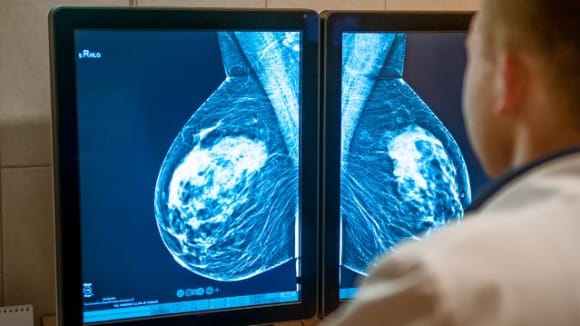

Radiographie : permet une première visualisation des structures internes du corps et peut aider à détecter certaines anomalies. Par exemple, la mammographie est couramment utilisée dans le dépistage du cancer du sein.

Échographie : utilise les ultrasons pour examiner les tissus et préciser la nature d'une lésion, notamment dans le cadre des cancers mammaires.